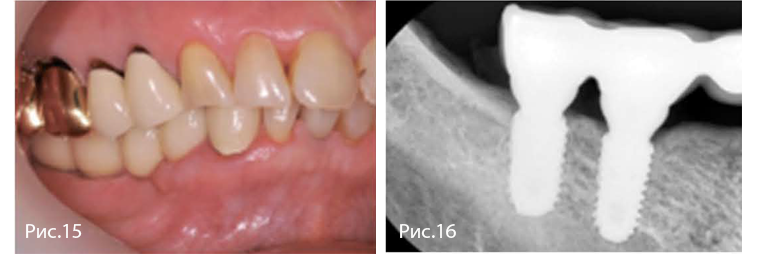

Рис. 15—16. Окончательное протезирование через 14 недель после имплантации. Отмечают благоприятное состояние мягких тканей в области вмешательства. Через один год уровень краевой кости и костная поддержка имплантатов стабильны.

Рис. 15—18. Окончательное протезирование через 14 недель после имплантации. Ширина гребня и объем кератинизированной десны стабильны. На КТ отмечают оптимальную костную поддержку имплантатов в области первого премоляра и первого моляра.